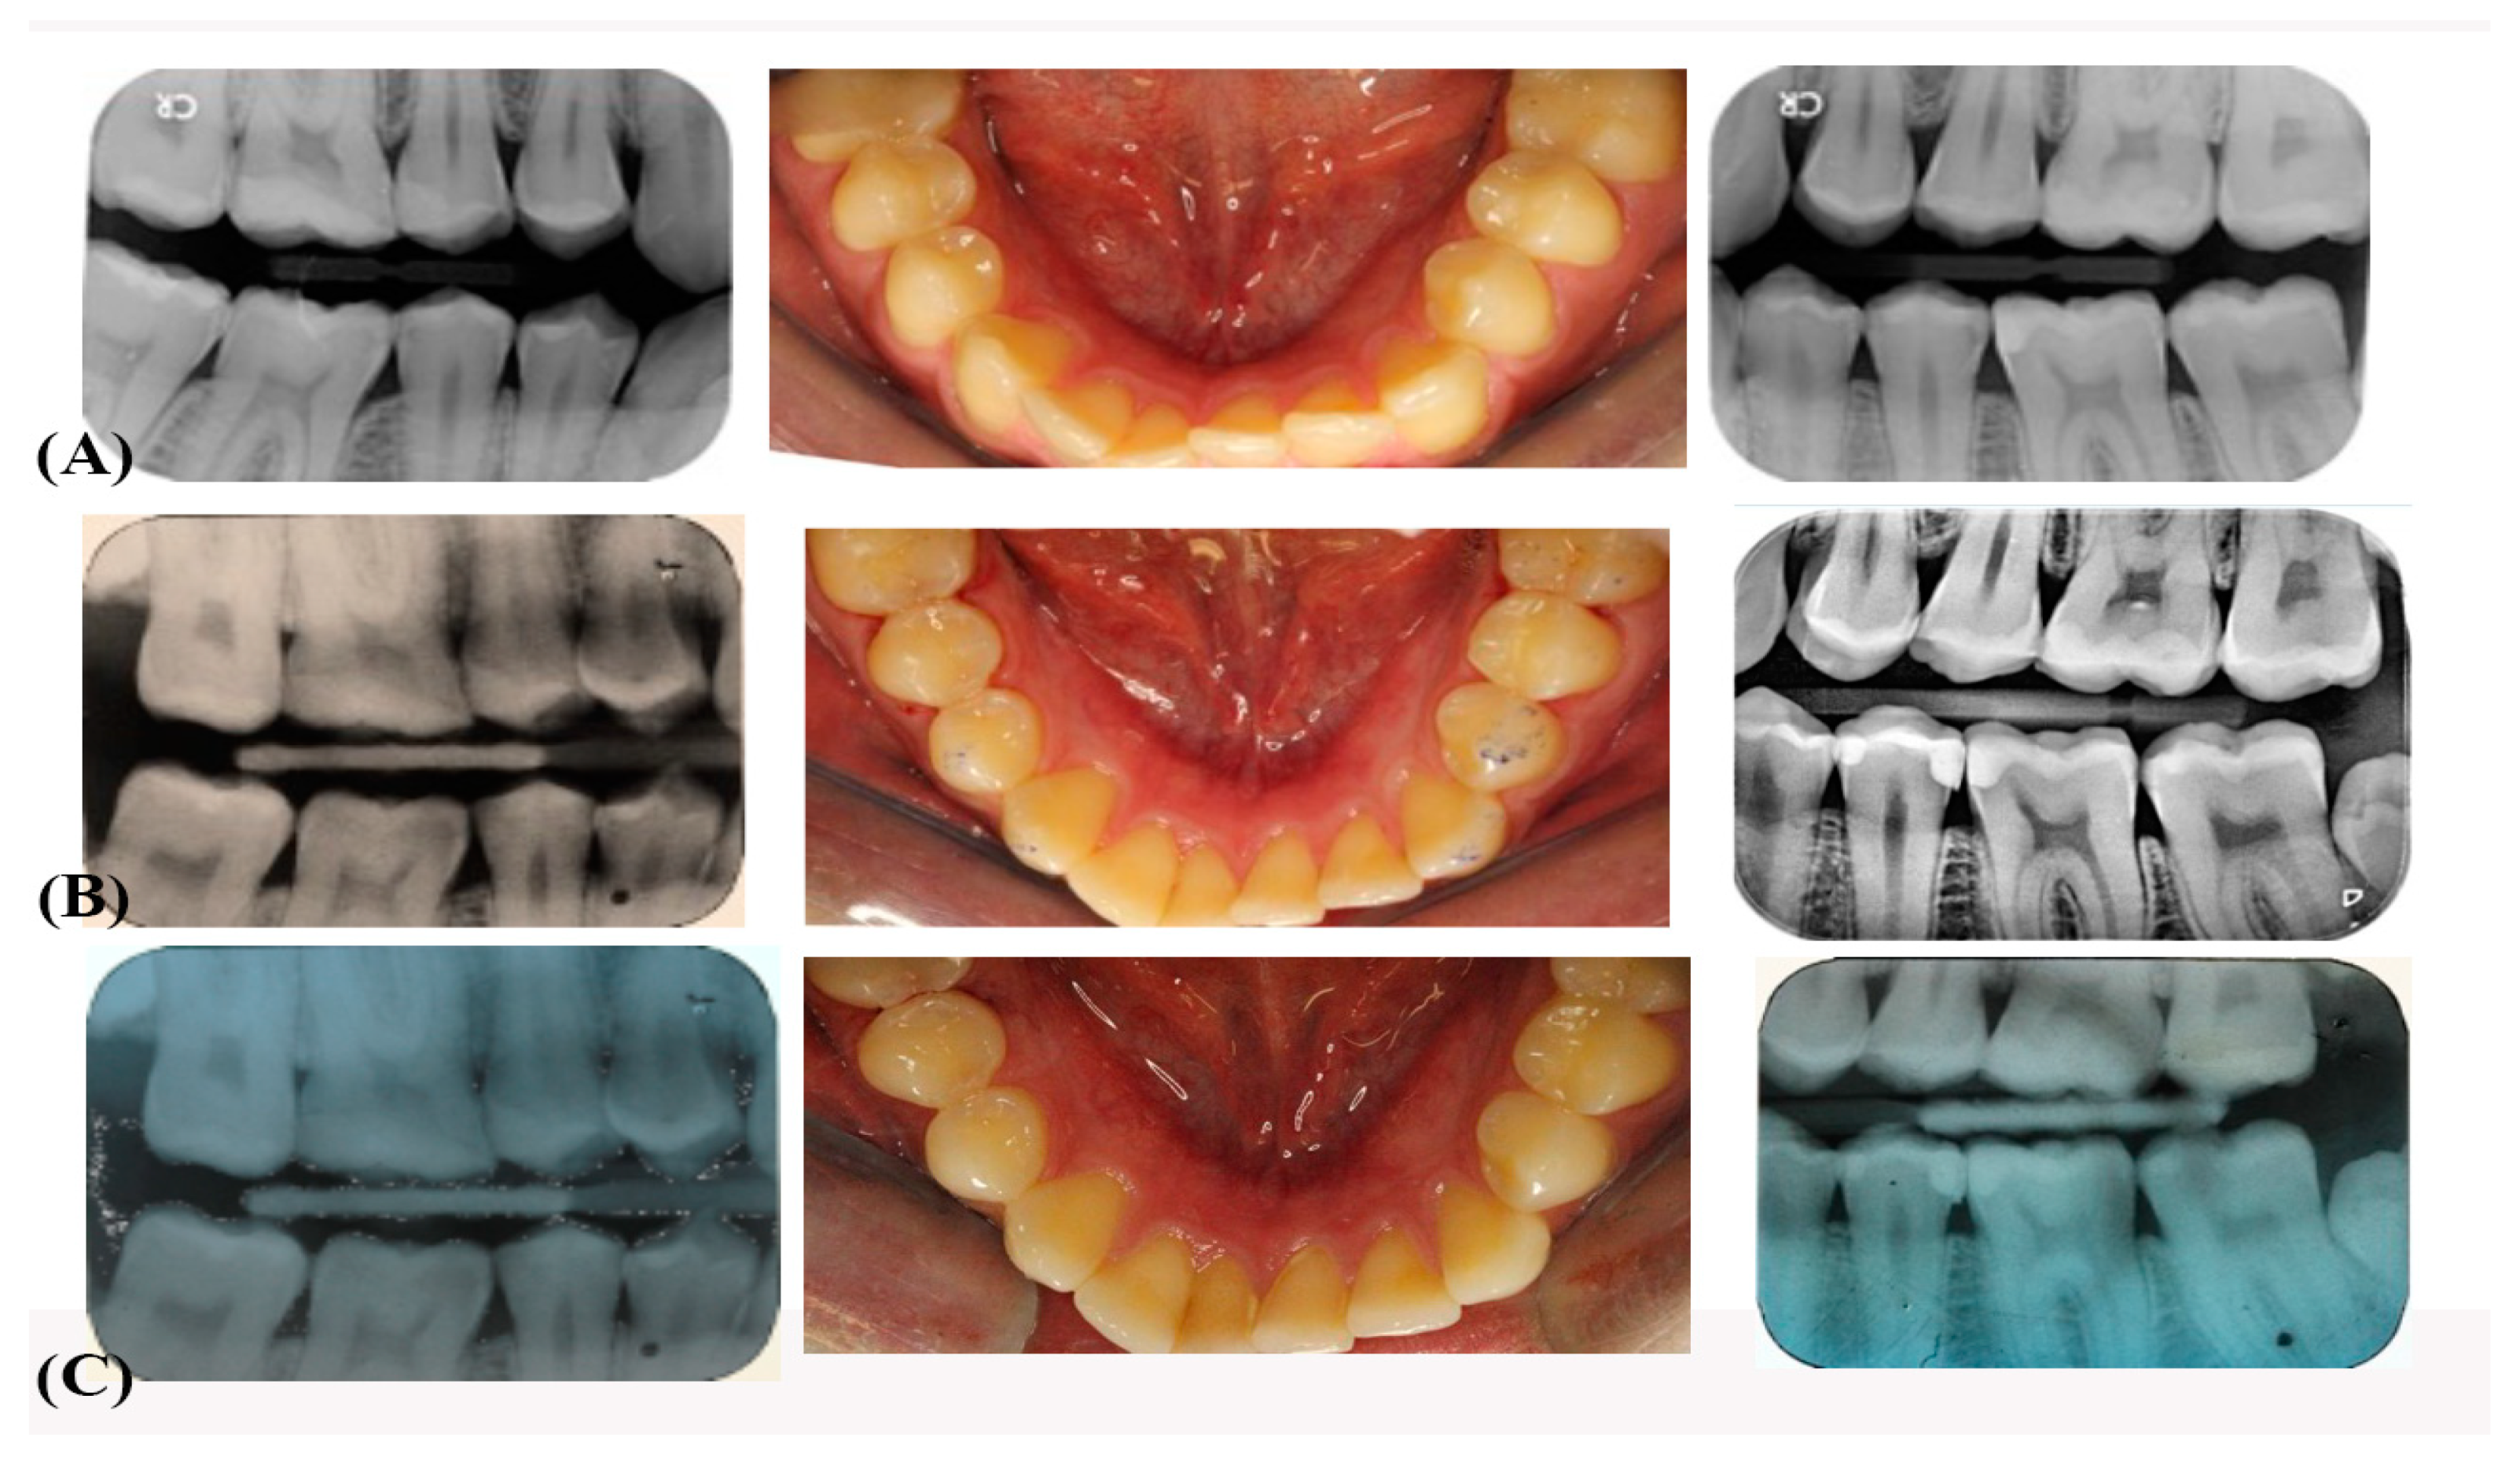

3.1. Esthetic Criteria

3.2. Biological Criteria